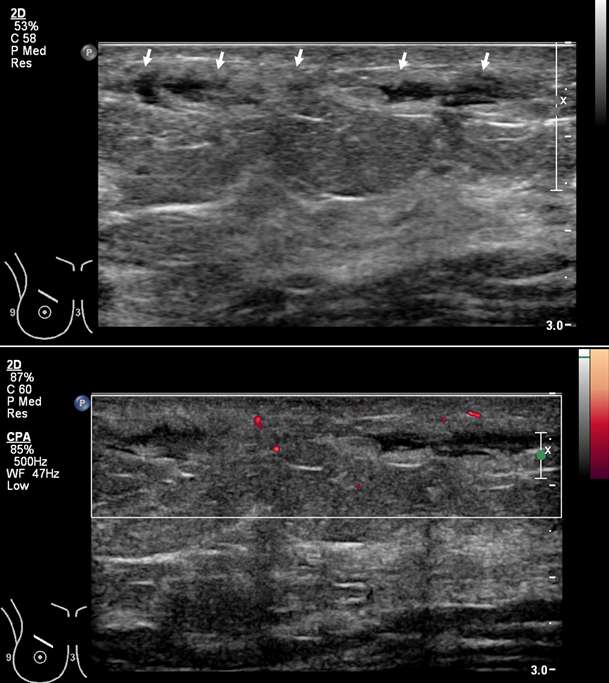

Figure 3B. Superficial thrombophlebitis. Grayscale (top) and power Doppler (bottom) sonography in the same patient shows a dilated and irregular tubular structure with adjacent wall thickening and inflammation (arrows) over the superficial/anterior upper right breast corresponding to the area of palpable abnormality and mammographic finding. Dopper imaging shows no flow within the structure, and live compression views (not shown) demonstrated a lack of compressibility, compatible with Mondor disease.